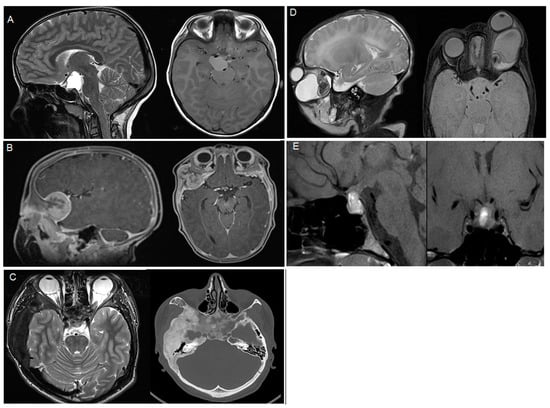

Craniopharyngiomas (all adamantinomatous) were the most common pathology (n = 4, 23.5%), while Rathke’s cysts, osteopetrosis, dermoid cysts, and teratomas were the second most common pathologies (n = 2, 11.8%, each, Table 1). An overview of the pathologies included, with representative imaging, is shown in Table 1 and Figure 1.

Figure 1.

Representative imaging of the included pathologies, (A) adamantinomatous craniopharyngioma, (B) melanotic neuroectodermal tumor, (C) fibrous dysplasia, (D) teratoma, (E) prolactinoma.